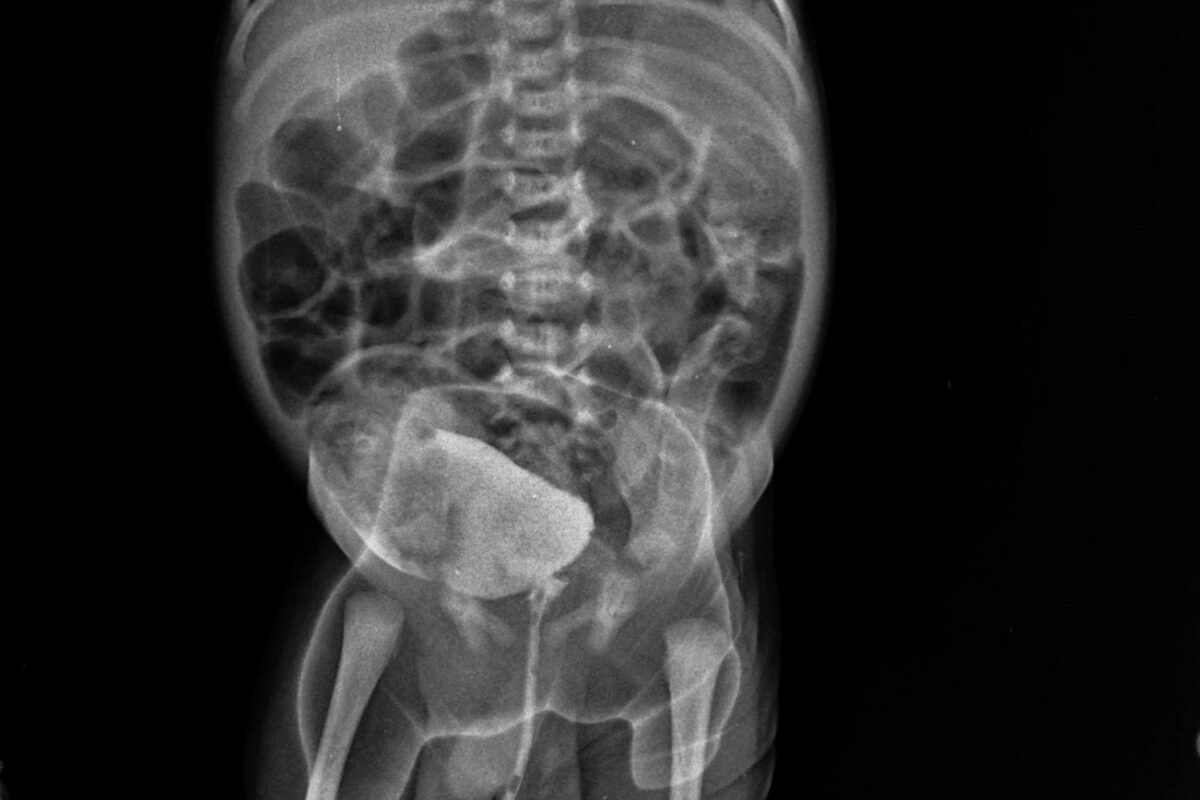

Parents visited at the clinic with patient. He is doing excellent. There is no complaints related to bowel. Child is passing stool regularly. Dr Ravi advised to undergo a Barium Enema X ray for child to rule out any stricture or narrowing/distension at colon. Today parents visited at our clinic to get treatment of their elder child whi is suffering with learning disability, with a ray of hope.